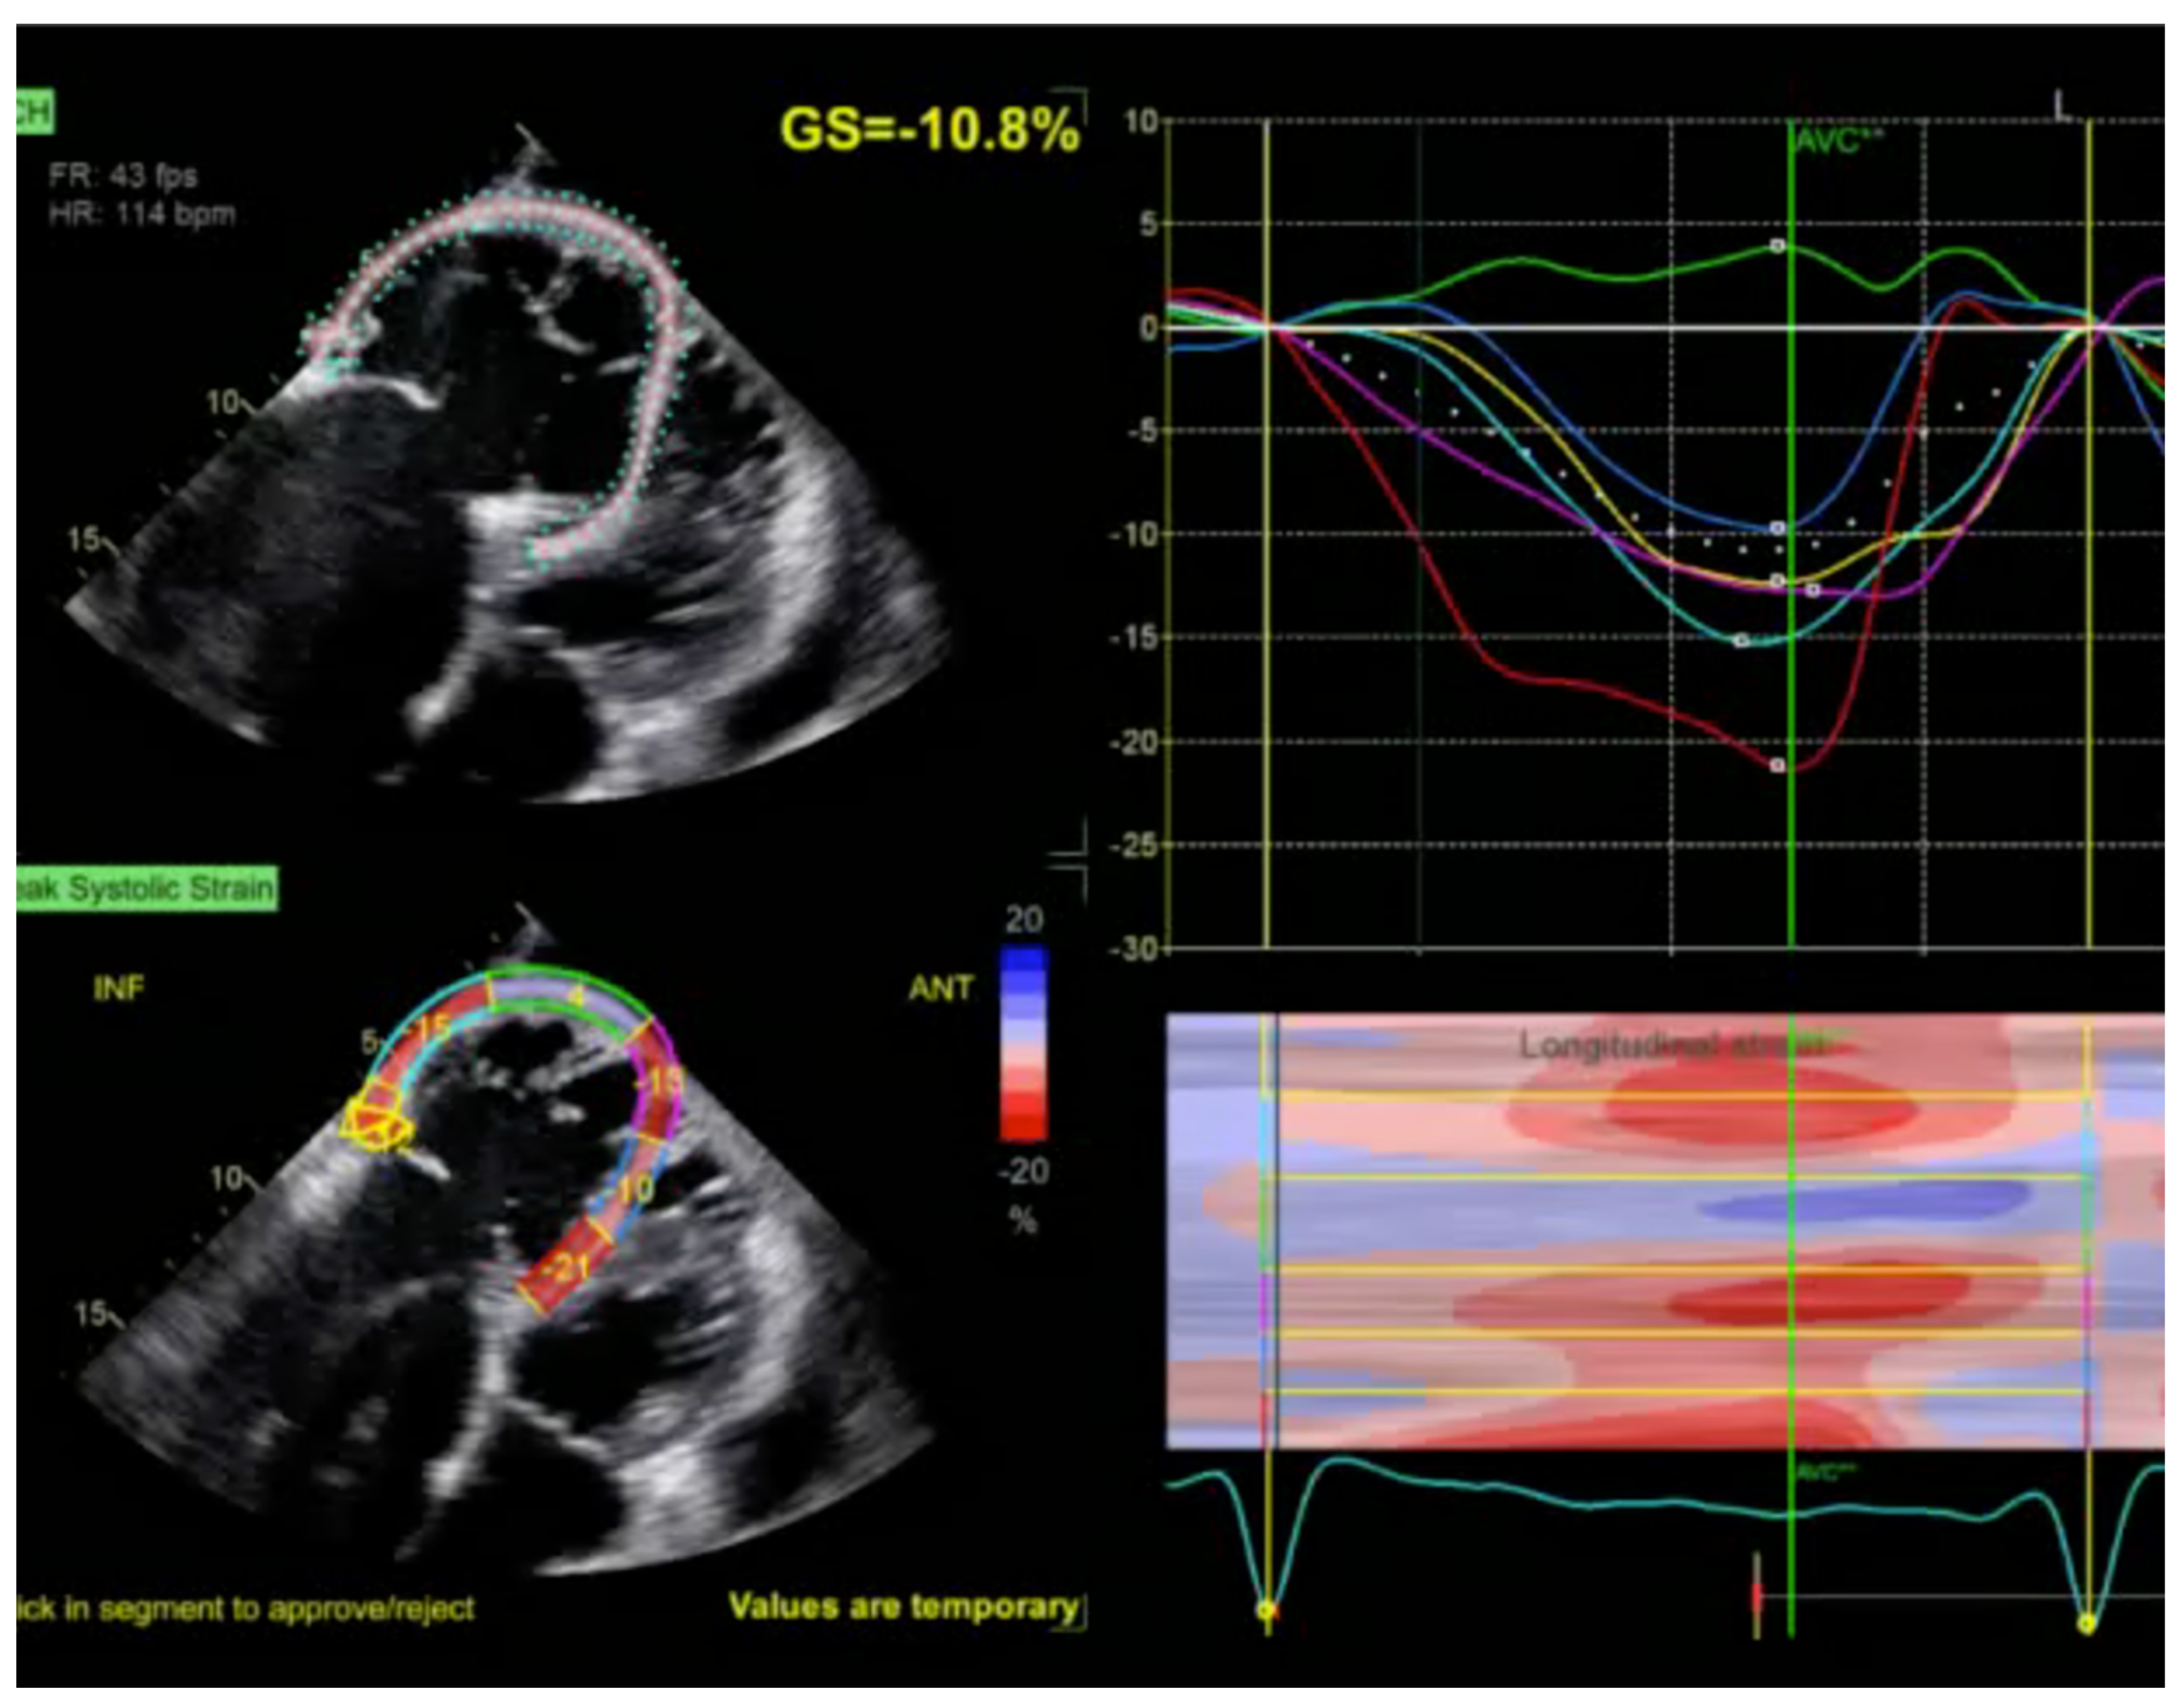

2.1. Echocardiography: The First Line of Diagnosis

- Gherbesi, E.; Gianstefani, S.; Angeli, F.; Ryabenko, K.; Bergamaschi, L.; Armillotta, M.; Guerra, E.; Tuttolomondo, D.; Gaibazzi, N.; Squeri, A.; et al. Myocardial strain of the left ventricle by speckle tracking echocardiography: From physics to clinical practice. Echocardiography 2024, 41, e15753. [Google Scholar] [CrossRef]